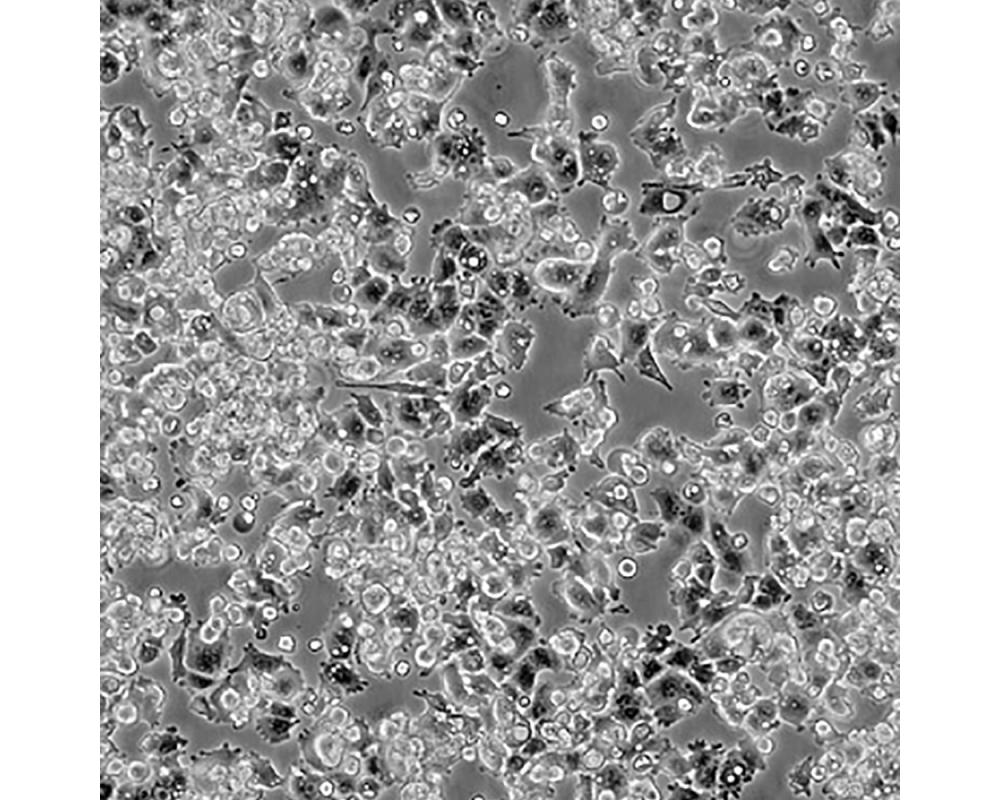

中文名稱 人肺腺癌細胞

組織來源 肺腺癌;男性

生長特性 貼壁

培養基 1640,90%;FBS,10%;雙抗。

培養條件 Atmosphere: Air, 95%; CO2, 5%。Temperature: 37℃